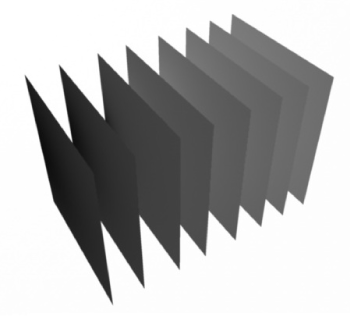

Volumetric Rendering is a popular means of visualization in medical studies [8,9]. It can be used for projecting 3D data into a 2D image. This technique has some variants, one of which is Volumetric Slicing; details of this process are discussed below. Volumetric data is a three-dimensional discretized grid structure in which space is partitioned into equal-sized volume elements (voxels). The voxels are typically cubes or parallelepiped structures. Each voxel has some data associated with it. Here each voxel need only contain a single value (which may be considered as density values).

Generation of Volumetric Data

The ultrasound dataset we used was provided by staff physicians at Penn Presbyterian Medical Center, University of Pennsylvania. It contained a set of ultrasound images of the femoral nerve. The images were taken along short axis of the femoral nerve serially at 5 mm spacing. The basic mechanism of generating volumetric data from images is simple. The width and height of the grid is same as the width and height of the given images. The depth of the grid (Figure 4) is equal to length of the femoral nerve scanned, which can be calculated by:

Figure 4: Volumetric Data Generation

Figure 5: Volumetric Data Generation

depth = (number of images - 1)*(distance between images)

Given this grid size, we can still choose the number of voxels to be fitted into this grid along each direction. For maximum visual accuracy, the number of voxels along each direction was set equal to the number of pixels along each direction. This simply gives the number of voxels along the width and height, leaving just the depth dimension. Our images are 640 x 480 and represent a physical area of 38 mm x 27 mm. Using basic proportionality, the number of voxels along the depth is:

Now that the grid size and number of voxels have been decided, the next step is to identify or compute the densities present in each voxel. It is easy to determine the density contained in those voxels where image data is directly available. Since the input images are in gray scale, densities can be found by scaling the gray scale value of each pixel to the range 0 to 1. The density of voxels in between two images is calculated by simple linear interpolation of the voxels in the corresponding position in the two neighboring planes. Practically storing the entire grid is infeasible because it is too big to fit into cache memory and will slow down the entire system. So, only the voxels which are present in one of the image planes are stored. If voxels between images are needed, then the inexpensive linear interpolation is performed instantaneously.